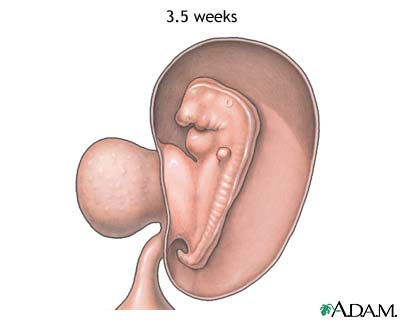

- Week 5 is the start of the "embryonic period." This is when all the baby's major systems and structures develop.

- The embryo's cells multiply and start to take on specific functions. This is called differentiation.

- Blood cells, kidney cells, and nerve cells all develop.

- The embryo grows rapidly, and the baby's external features begin to form.

- Your baby's brain, spinal cord, and heart begin to develop.

- Your baby's gastrointestinal tract starts to form.

- It is during this time in the first trimester that your baby is most at risk for damage from things that may cause birth defects. This includes certain medicines, illegal drug use, heavy alcohol use, infections such as rubella, and other factors.

Weeks 6 to 7

- Arm and leg buds start to grow.

- Your baby's brain forms into 5 different areas. Some cranial nerves are visible.

- Eyes and ears begin to form.

- Tissue grows that will become your baby's spine and other bones.

- Your baby's heart continues to grow and now beats at a regular rhythm. This can be seen by vaginal ultrasound.

- Blood pumps through the main vessels.